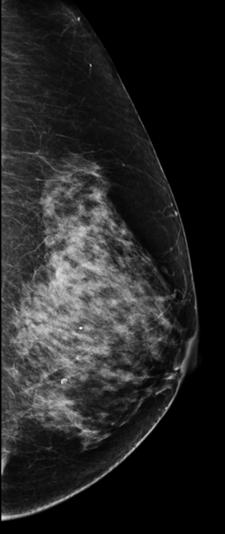

Te hemos hablado de mamografía, pero te preguntarás: ¿qué es? La mamografía es una técnica radiológica especializada que utiliza rayos X para obtener imágenes precisas del tejido mamario. Se emplea principalmente para el tamizaje y diagnóstico del cáncer de mama.

Durante este examen, la paciente se coloca frente a un aparato de rayos X de baja dosis, diseñado especialmente para comprimir las mamas entre dos placas. Esta comprensión ayuda a extender el tejido mamario, lo que garantiza la obtención de una imagen nítida de las estructuras internas de la mama.

En este contexto, la mamografía de tamizaje es una herramienta esencial para la detección temprana en mujeres asintomáticas y el radiólogo es el encargado de su interpretación. Además de esta técnica de imagen, se realizan otros estudios, como ecografías mamarias, resonancias magnéticas y biopsias guiadas por imagen. Estos estudios complementan la información proporcionada por las mamografías, al ofrecer detalles adicionales sobre las características de las lesiones en caso de obtener un resultado positivo.

La densidad mamaria se refiere a la cantidad de tejido glandular* presente en las mamas de una mujer. Cuando un seno tiene una mayor proporción de tejido glandular en comparación con el tejido graso*, se considera que tiene una densidad mamaria alta.